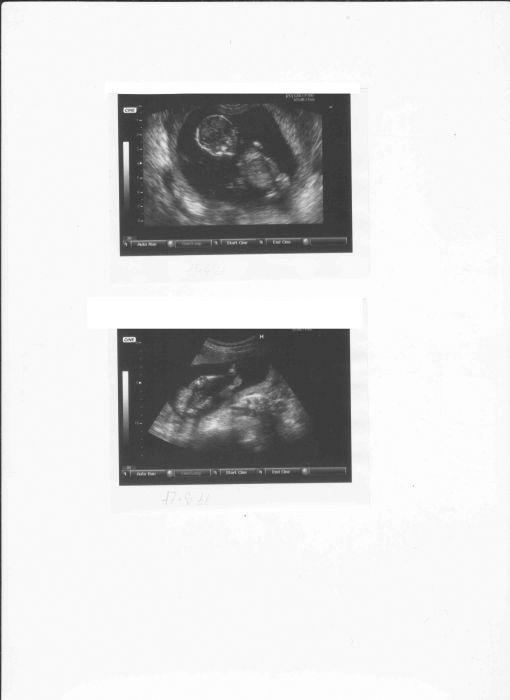

U těch dvou obrázku nahoře 13+4 a dole dnešek 17+6, u té dnešní je zadeček,nožičky, kolínka a pupeční šňůra